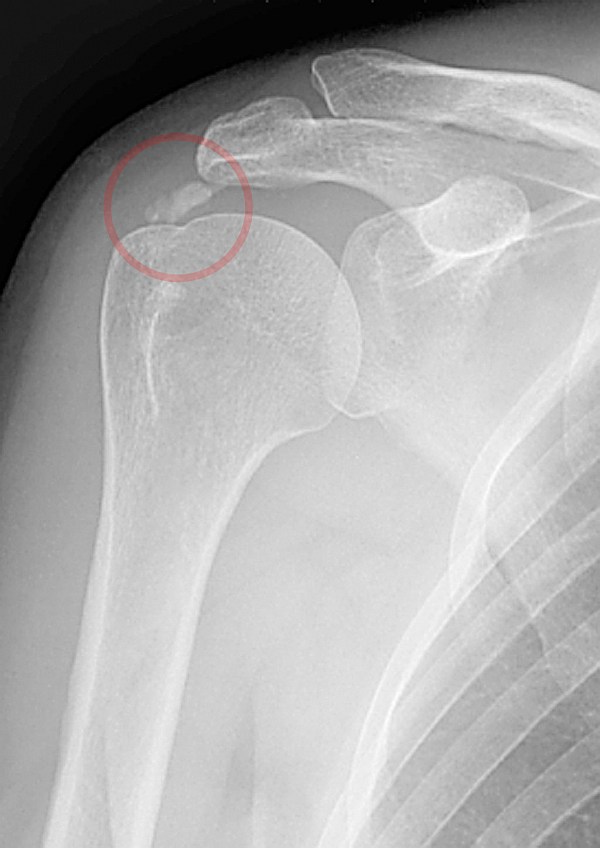

4、年龄较大或病程较长者,X线平片可见到肩部骨质疏松或冈上肌腱、肩峰下滑囊钙化征。